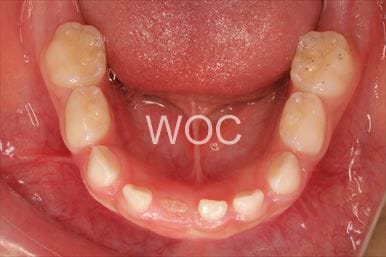

治療前1

治療前2

治療前3

- 年齢:8歳1ヶ月

- 主訴:下の歯が見えない、ガタガタ

- 診断名:過蓋咬合、叢生

- 装置:機能的矯正装置

- 期間:2年4ヶ月 ※

- 費用:基本矯正料金:390,000円